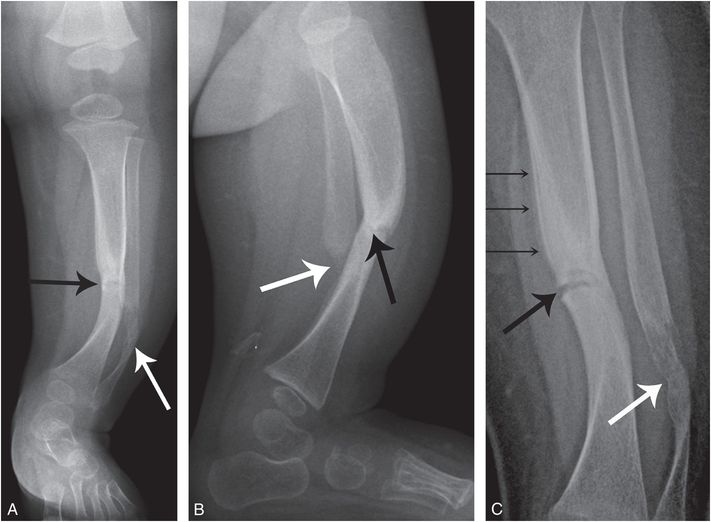

Polat s., aksoy e., serin g.m., yıldız e., tanyeri h. Angioma formation in connection with hypertrophy of limbs and hemihypertrophy. Individual mesothelial markers are of low sensitivity and specificity for mesothelioma. This may lead to severe pulmonary encasement with resulting ventilatory impairment. Carl m., stroebel w., rassner g., garbe c. On upright views, the opacification is particularly marked in the laterobasal hemithorax with blunting of the costophrenic angles. Willam c., maurer j., steinkamp h.j. Mesothelial mesothelioma the differential diagnosis of this common form of mesothelioma is extremely difficult. Ct in differential diagnosis of diffuse pleural disease. Difficulties in the differential diagnosis of granulomatosis with polyangiitis and scarring pemphigoid. Neuroradiological assessment and differential diagnosis. Most tumors arise from the pleura, and so this article will focus on pleural mesothelioma. Pleural thickening or recurrent pleural effusion on chest xray followed up with contrast enhanced chest ct scan.